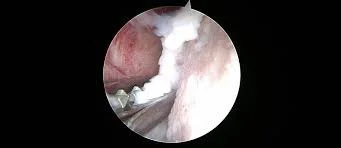

OCD scope of joint

Osteochondritis dissecans is a developmental joint disorder that occurs when cartilage does not properly transform into bone during a dog’s growth. Normally, cartilage gradually hardens into bone as a puppy develops. However, in dogs with OCD, this process fails in certain areas of the joint.

As the cartilage thickens and weakens, it may crack or detach from the underlying bone, forming a loose cartilage flap. This flap can move within the joint space, leading to inflammation and pain.

In some cases, advanced imaging such as CT scans or arthroscopy may be used to evaluate the joint more thoroughly.

The goal of surgery is to remove the damaged cartilage flap and smooth the joint surface. This allows healthy cartilage to develop and reduces joint irritation.